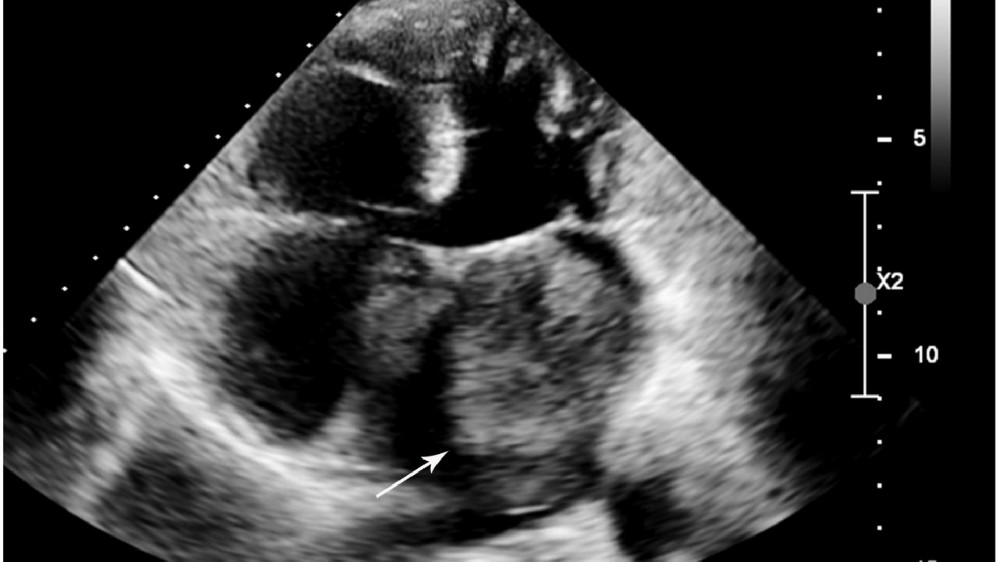

心臟癌(心臟肉瘤)的分期和存活率

瞭解不同階段有助於釐清預後、決定治療方法,以及管理診斷出患有下列疾病的病患的期望值 心臟癌(心臟肉瘤).準確的分期有賴於影像研究、病理評估和臨床參數,以協助醫療團隊發展個人化治療,確保最佳效果。

腫瘤完全位於心臟組織內,一般較小且控制良好。

無轉移;心臟結構的功能損害最小。

首選的治療方式包括手術切除腫瘤和針對性的局部治療,通常只需最低限度的廣泛全身性治療。

根據香港腫瘤內科資料庫(HKMOR)的資料,2024 年的存活率為 85%,而早期診斷及手術治療的存活率則相對較高,一般超過 85% 的五年存活率。